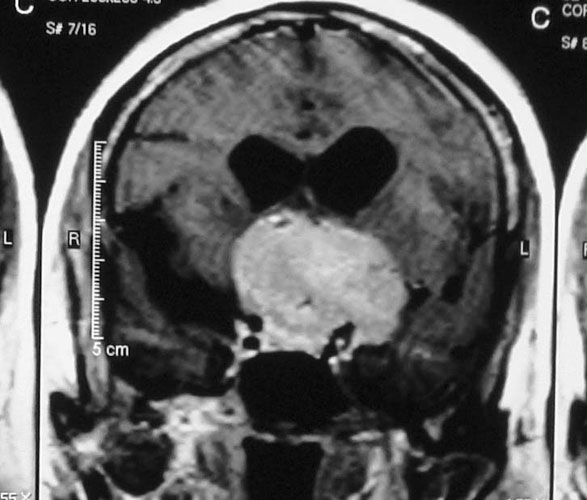

Arteriovenous malformations

Arteriovenous malformations of the brain are abnormal bunch of blood vessels that can rupture causing bleeding, or may cause seizures. Brain imaging (CT, MRI) is required for early diagnosis, while definitive treatment is carried out after cerebral angiography. Treatment implies craniotomy and excision of the AVM, which can be done safely in majority of the cases. Embolisation and radiosurgery are acceptable substitutes, but carry risk of further bleeding.